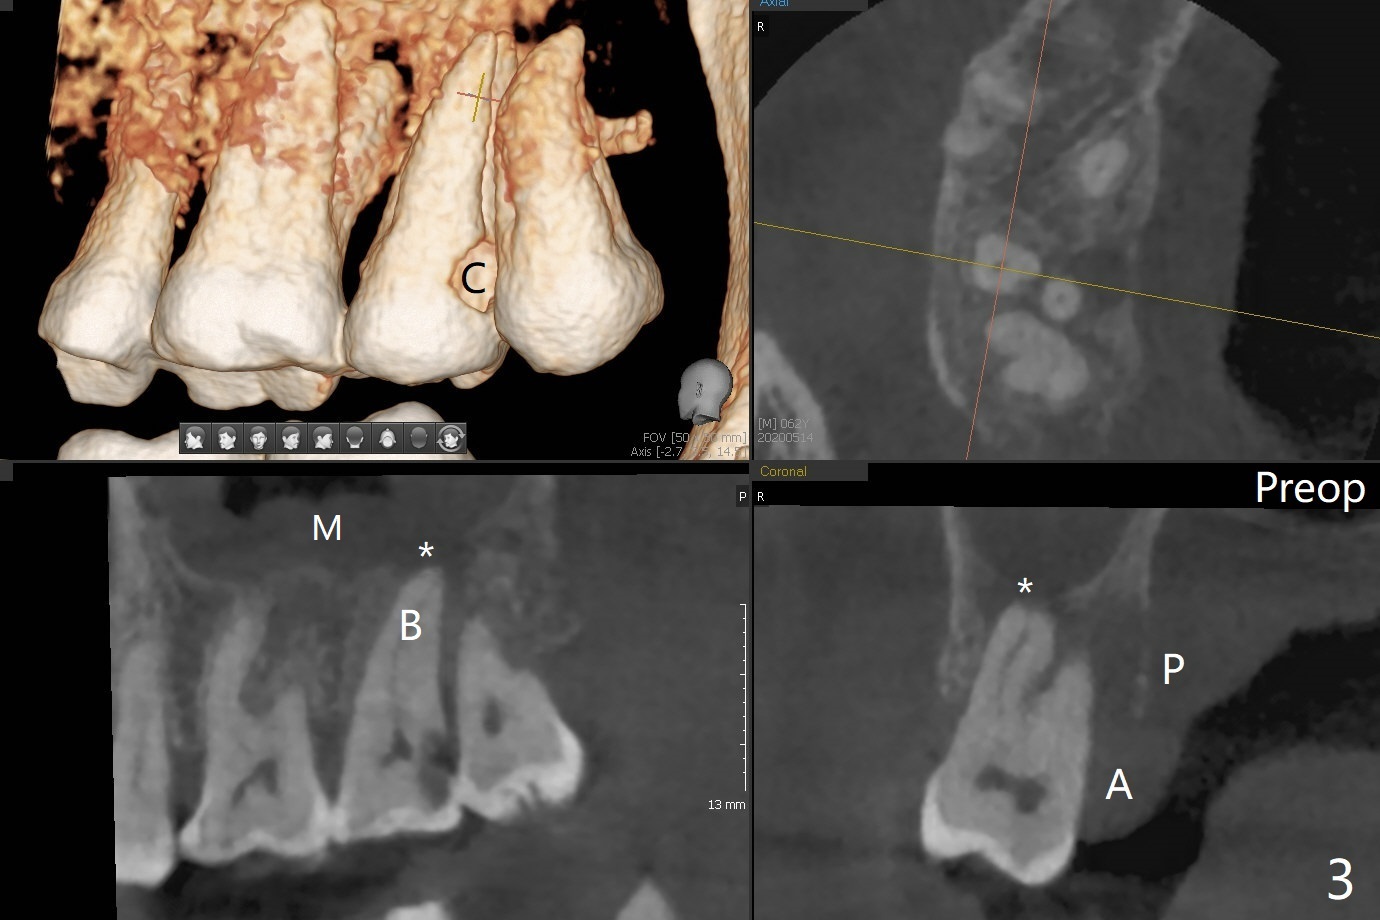

A 62-year-old man has palatal abscess with deep pockets (Fig.1 A) at tooth #2 with DO caries (Fig.2 C). The patient agrees with extraction and bone graft. Preop CT shows the palatal (P) wall defect and buccal (B) socket perforation (Fig.3 *). It should be easy to do sinus lift with the thick sinus membrane (M). To maximize hard tissue regeneration, GEM21S is used to hydrate ground cortical chips (particle size: 125μm – 850μm)) and cortical/cancellous allograft (.5-1 mm) for socket preservation (Fig.4 G) and sinus lift in the buccal socket (^). Due to swollen soft tissue and overpacking, the bone height increases (Fig.5 arrow). The socket opening is closed with GEM Cap and Perio Glue as well as perio dressing.